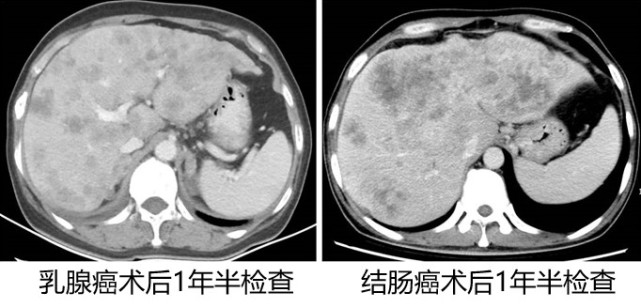

图片(患者术后复查的影像记录,肝上的大片阴影皆为转移灶)

相反的,像这两位患者,左图是乳腺癌患者的,术后一年半才复查;右图是结肠癌患者的,也是一年半以后复查,结果一看满肝都是转移,这个时候再治疗就比较困难了。当然我们也有各种药物,但是效果肯定没有及时发现的好。

所以医生会根据患者病情,肿瘤进展的情况开具相关检查,并根据复发风险的预测决定复查的时间间隔。因此如果自己信任的经治医生给您开了相关检查,就要按照医生的要求去定时、规范地检查,早期检出可能的复发,取得更好疗效和长期生存。